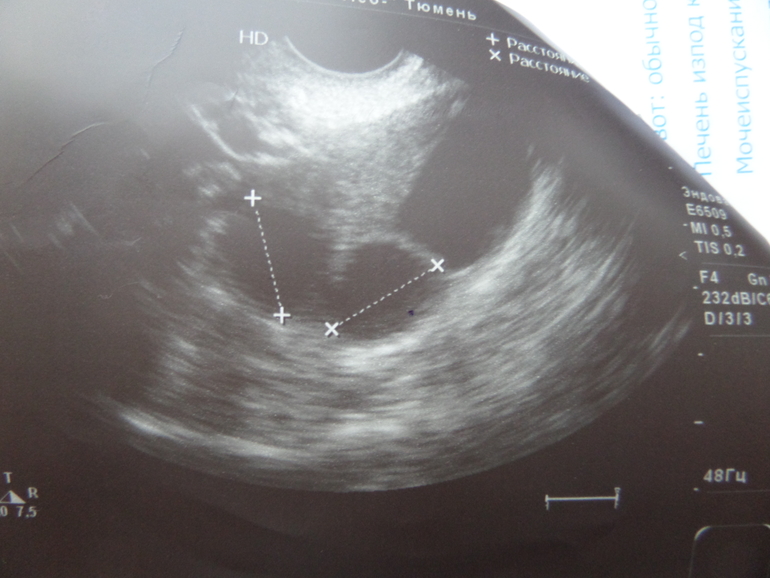

В понедельник на узи было два фолликула 16,17 мм и один за ними ваще большой, где то 20 мм. Думала может тот большой лопнул, если бы было так то и БТ бы выросла.

снимок узи